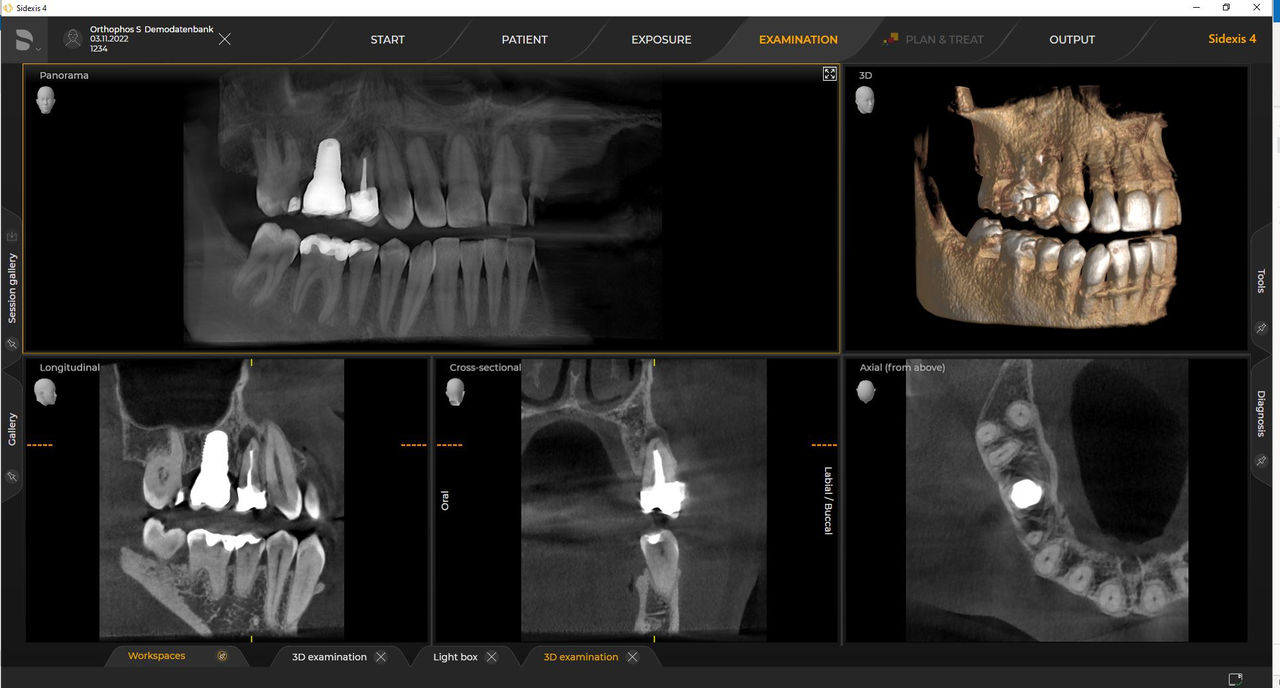

Dentsply Sirona-röntgeneenheden werken uitsluitend met Sidexis 4. Toch is de gegevensmigratie van Sidexis XG naar Sidexis 4 heel eenvoudig. Sidexis 4 zorgt voor een volledige digitale ervaring met de nieuwste tools

Orthophos S 2D maakt een 3D-upgrade mogelijk. Axeos is een speciale hybride unit. De Orthophos E heeft deze optie niet.